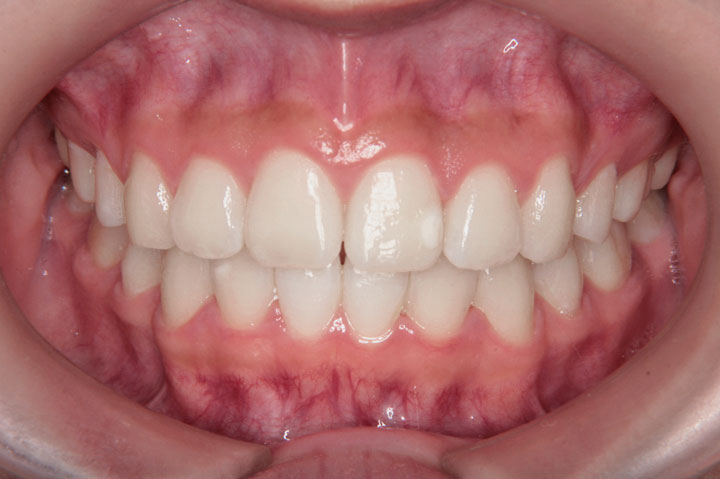

上顎前突(出っ歯)

前歯部不正(交叉咬合など)

上顎前突と叢生を気にされて来院された小学校4年生の女子の患者さんです。第一段階として、ヘッドギアーによる上顎大臼歯の遠心移動ををはかり、奥歯の関係を整えた後、上下顎小臼歯を抜歯いただきデーモンシステムで後期治療を行いました。前期治療に約1年、定期観察を経て、エッジワイズ治療に2年を要しており、その後保定に移行しております。